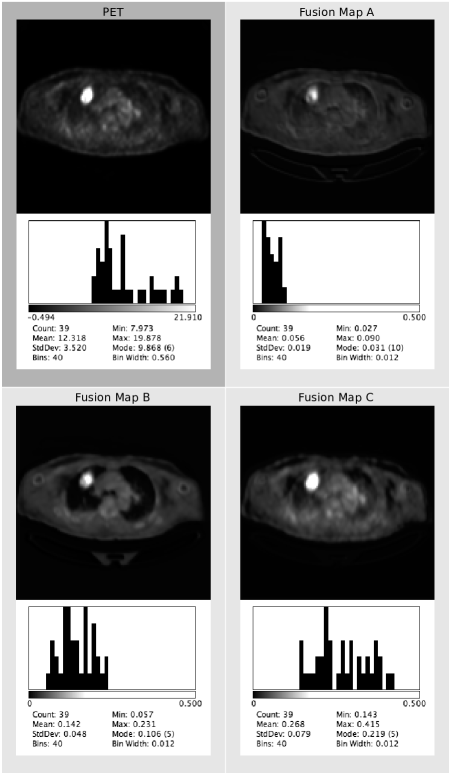

We extracted the feature fusion maps produced by the co-learning unit (see Section II-D) to examine the fusion ratios that were produced for an image with a tumor inside the lung field. This experiment was undertaken to confirm whether the fusion ratios that were automatically derived matched the well-established expectations. Further analysis on a heterogeneous tumor was performed for the Supplementary Materials (see Section S3). We also visually compared the results derived using our co-learning CNN’s spatially varying fusion to the results derived from using different uniform fusion ratios with the FS architecture. We used uniform fusion ratios that included mainly anatomical information (30% PET with 70% CT), equal information (50% PET and CT), and mainly functional information (70% PET with 30% CT).

Fig. 7 depicts the co-learned fusion maps that were derived for an image with a single tumor; a larger version is included as Fig. S5 in the Supplementary Materials. In the figure, each feature map channel has been independently normalized so that their real valued pixels could be viewed in the paper. In any particular channel, a higher absolute intensity implies a greater importance placed on that pixel during fusion. The figure shows how different information is prioritized differently for each region. For example, the 7th CT fusion channel (row 1, column 7) places a greater emphasis on the lungs while the 26th PET fusion channel (row 8, column 2) places the greatest emphasis on the tumor. The figure also indicates that the fusion weights are derived from features of both modalities. For example, the 7th CT fusion channel (row 1, column 7) emphasizes the lungs including the area that contains the tumor. Meanwhile, the 13th CT fusion channel (row 2, column 5) also emphasizes the lungs but de-emphasizes the area containing the tumor. Further analyses are included in Section SIII of the Supplementary Materials.

The fusion maps shown in Fig. 7 demonstrate that our co-learning CNN can derive spatially varying fusion maps for images that contain multiple structures that have different fusion requirements. Our CNN does not need to divide the problem into distinct tasks for each ROI but rather can derive the relevant fusion information in an end-to-end manner. For example, the 7th CT fusion channel (row 1, column 7) and the 13th CT fusion channel (row 2, column 5) emphasize the lung fields relative to the area containing the tumor. We suggest the co-learning unit has produced these specific fusion channels because (in combination with other channels) they contain information to distinguish the lung fields from any tumors they may contain. It is well-established that the lung fields can be identified using CT data alone [57], and it was expected that the co-learning CNN would operate in a similar fashion. The fusion maps automatically derived by our co-learning CNN prioritize the CT data for the lung field ROIs, consistent with this expectation. Similar patterns for lung fields are noticed in the fusion maps of other PET-CT images.

While it may appear that several channels in the fusion map are redundant (similar in appearance to other channels), this is merely a visualization issue caused by normalizing 32-bit floating point greyscale images for display within the paper. As shown in Fig. S4 in the Supplementary Materials, PET fusion channels 33 to 37 (row 13, columns 1 to 5) appear visually similar but closer examination of the distribution of fusion weights within the images indicates that each channel prioritizes information in subtly different ways. Section SIII in the Supplementary Materials contains a detailed example showing the differences in these visually similar fusion channels and their impact in the analysis of heterogeneous tumors, which is an important clinical application. We suggest that the capacity of our co-learning CNN to derive these subtly different fusion weights enables more precise integration of the complementary information in each modality when compared with uniform fusion (see Fig. 8).